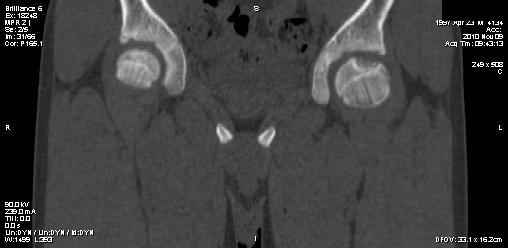

Мальчик 13 лет. В течение нескольких месяцев беспокоят боли в левом тазобедренном суставе.

При обследовании выявлена киста шейки левого бедра с сопутствующими изменениями в головке бедра, которые мы трактуем как дистрофические. Планируем вскрытие и санацию полости кисты передне-боковым доступом, костную пластику. Перед нами возникли следующие вопросы: для пластики использовать крыло подвздошной кости либо большеберцовую кость,либо их комбинацию, (полость большая,одним крылом можно не обойтись) или донорский аллотрансплантат с Коллапаном? Фиксировать ли? Если фиксировать, то чем? Доступны обычные угловые пластины либо АВФ.

Ув. Сергей! Д-з: или солитарная киста, или аневризмальная (есть небольшое "вздутие") или остеобластома ( старое название "остеобластокластома"). Если 3 вариант то полость надо обработать спиртом или азотом. Предпочтительнее аутопластика из 2 подвздошных костей. Так как срок фикс. длительный то АВФ субоптимален. Предпочтительнее фиксация угловой нестандартной пластиной 110-115 град ("разогнутая" 95 град).В запасе минимум 3 пластины с 3 типоразмерами клинка (расстояние от tuberc. innominatum до перехода метаэпифиза в нижний полюс головки).Ножка: минимум 3 винта в "здоровой" кости диафиза.Перед формированием канала пробойником 3 "страховочные" спицы: большой вертел центр головки (межвертельный перелом лучше перелома шейки) Аутопластика после МОС.